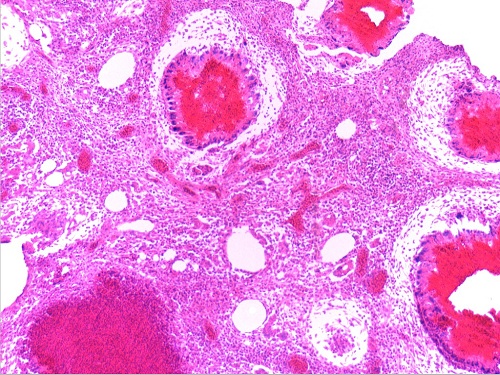

淋巴结大肠杆菌肉芽肿4(10X10)